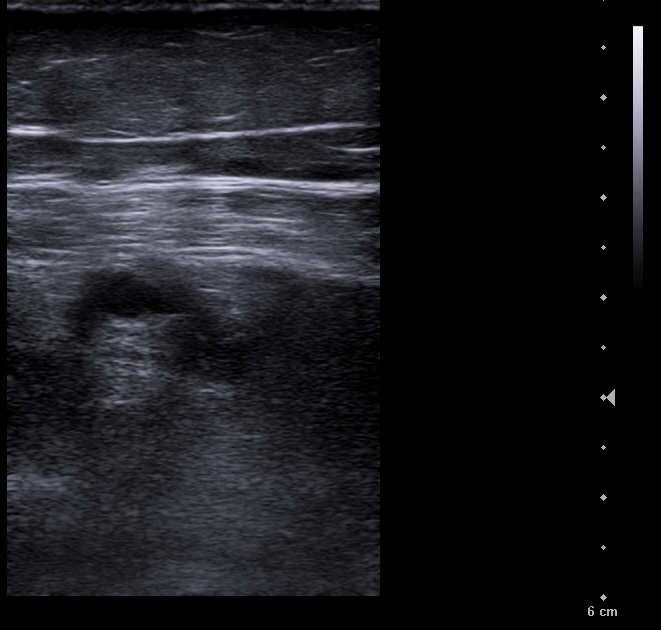

En la ecografía se aprecia vena femoral común, vena femoral superficial, vena safena mayor y vena safena menor con diámetro y flujo normal, llenado total de la luz venosa con el Doppler color y compresibilidad adecuada.

Vena poplitea no compresible, con material ecogénico en su interior y ausencia de flujo con Doppler color.